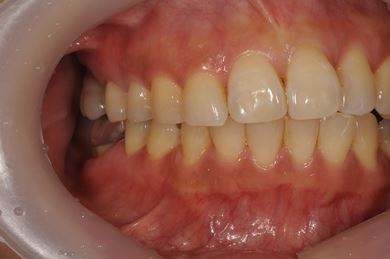

骨再生インプラント治療+セラミック治療+歯肉歯槽骨整形

| 性別/年齢 | 女性 / 42歳 | ||||||||||||||||||||||||||||||||

| 主訴 | インプラント治療を受けたい。 | ||||||||||||||||||||||||||||||||

| 治療方針 | 左上奥欠損部分をインプラント治療にて機能的・審美的回復を行う。 | ||||||||||||||||||||||||||||||||

| 治療内容 | インプラント2本(ソケットリフト)、メタルボンドセラミック3本(メタルボンド用土台1本)、歯肉歯槽骨整形 | ||||||||||||||||||||||||||||||||

| 総治療費 | 1,227,713円 | ||||||||||||||||||||||||||||||||

| 治療期間 | 11ヶ月 |